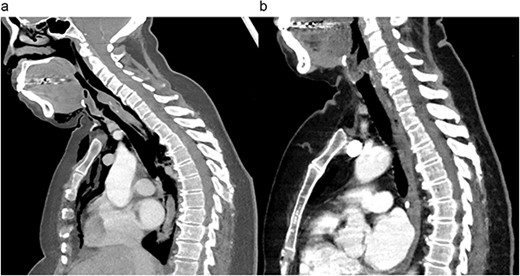

Within 12 hours of discharge, she was readmitted with dysphonia and florid oedema of the head and chest. A CT chest demonstrated a 6 cm laceration of the distal trachea 2 cm above the carina, with diffuse subcutaneous emphysema (Fig. 1a).

Preoperative (a) and postoperative (b) sagittal CT views of the thoracic cavity, demonstrating a large posterior tracheal defect extending to just above the carina, and its resolution postoperatively.

The patient had an uneventful postoperative recovery period. Follow up bronchoscopy 2 months later demonstrated a well-healed tracheal site.